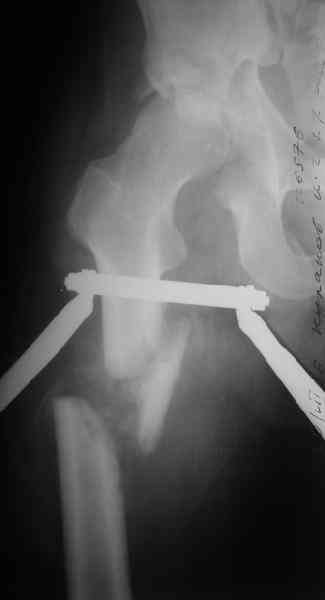

Отправитель: Maxim Agalakov 26 Июль 2006, 21:59

Здравствуйте Анатолий Федорович. Сегодня заситезировали этопу пациенту длинные трубчатые кости. В отношении вертлуги мы остановились на остеосинтезе вертлужной впадины из доступа Кохер -Лангенбек. Необходимость (и возможность) закрытого вправленя через месяц представляется сомнительной - даже если удастся - судьбу головки

это вряд ли изменит в лучшую сторону, а если вправить, то на нее будет осуществляться давление отломком,связанным с осевым скелетом. В дальнейшем, если возникнут ожидаемые проблемы с АНГБ, коксартрозом, вернямся к этому больному. (описанную вами операцию надо хоть посмотреть разок, наверняка есть какие-нибудь тонкости).